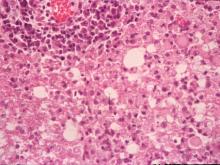

小腦:白質部呈現多發局部軟化脫髓鞘,血管周圍可見以淋巴球及單核球為主的血管周圍圍管現象。病灶區內神經膠質細胞增生,部份神經膠質細胞可見嗜酸性核內包涵體(圖3、4)。 2.